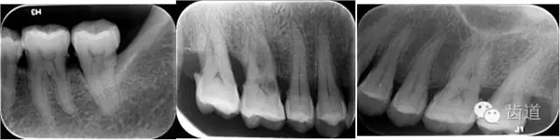

X線:根尖片、曲面斷層片(牙槽嵴頂,水平垂直吸收,程度)